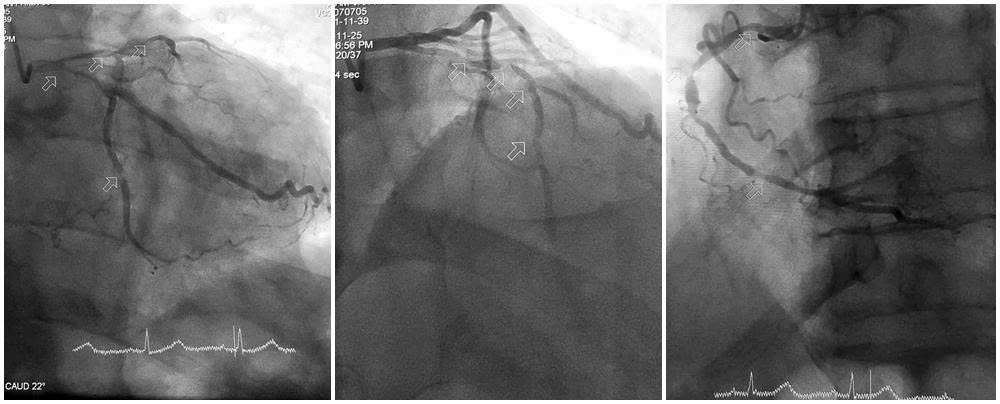

Với sự đồng thuận của gia đình, người bệnh lập tức được chuyển đến phòng can thiệp trong tình trạng huyết động không ổn định, chức năng tim suy giảm rõ rệt, đòi hỏi phải xử trí khẩn trương và chính xác. Kết quả chụp mạch vành cho thấy mức độ tổn thương nặng cả ba thân động mạch vành. Động mạch liên thất trước hẹp tới 90–99%, gần như tắc hoàn toàn; động mạch mũ và động mạch vành phải hẹp 80–90%, thành các mạch vôi hóa nhiều.

Hình ảnh tổn thương nặng 3 thân động mạch vành